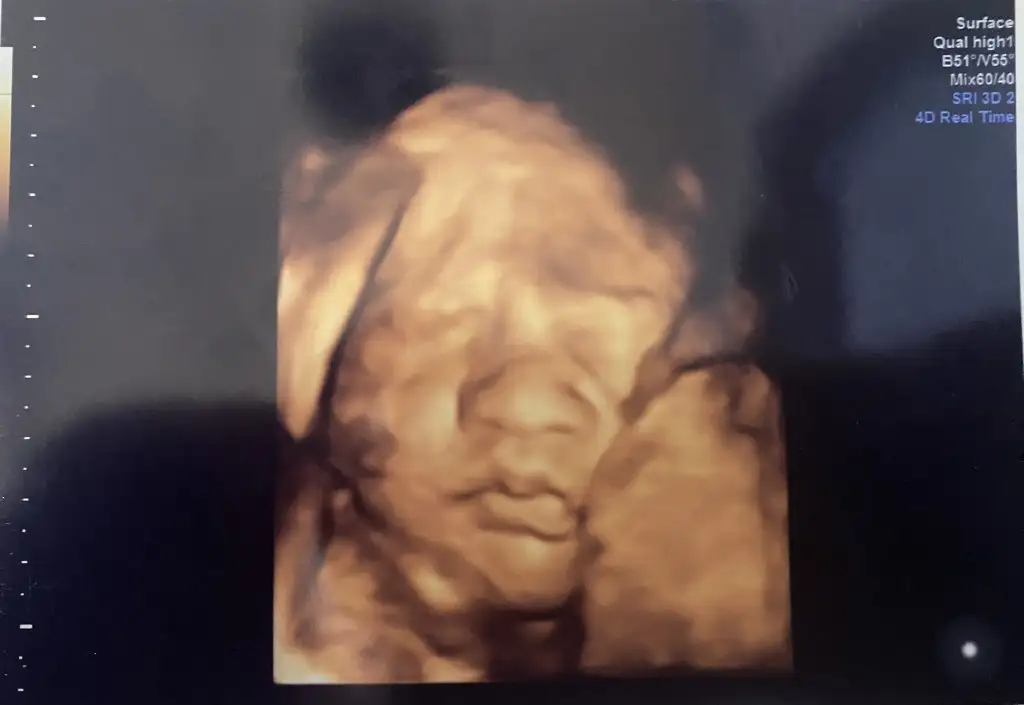

Ultrason cihazından rahatsız olan sinirli bir bey bırakıyorum

Bal suratEki Görüntüle 3435288 Bugün kontrolümüz vardı kızlar , 30+0 , 1500 kg , 41 cm olmuşuz . 33 . Haftayla nst e başlayacakmışız, temmuzda da sık sık görüşeceğiz dedi doktorum.